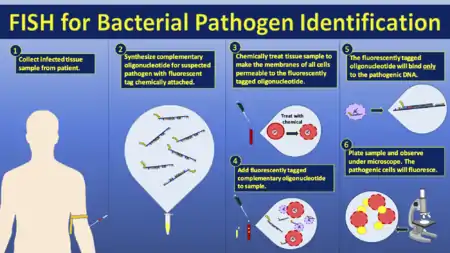

FISH has been extensively studied as a diagnostic technique for the identification of pathogens in the field of medical microbiology.[30] Although it has been proven to be a useful and applicable technique, it is still not widely applied in diagnostic laboratories. The short time to diagnosis (less than 2 hours) has been a major advantage compared with biochemical differentiation, but this advantage is challenged by MALDI-TOF-MS which allows the identification of a wider range of pathogens compared with biochemical differentiation techniques. Using FISH for diagnostic purposes has found its purpose when immediate species identification is needed, specifically for the investigation of blood cultures for which FISH is a cheap and easy technique for preliminary rapid diagnosis.[30]

.gif) Another schematic of FISH process.